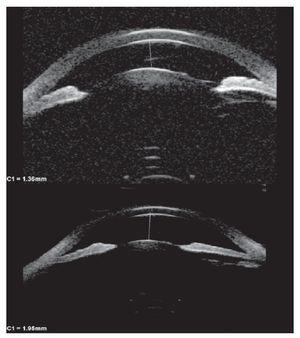

Hombre de 13 años de edad, sin antecedentes heredofamiliares ni personales patológicos de importancia. El motivo de consulta fue la disminución progresiva de la agudeza visual de meses de evolución, acompañado en ocasiones de dolor periocular intermitente. A la exploración física se encontró una talla de 1.52 m, la cual se encuentra dentro de la percentila 50 para la edad, así como una discreta braquidactilia en ambas manos. La exploración oftalmológica reveló: agudeza visual de 20/400 en ambos ojos y una agudeza visual mejor corregida de 20/30 y 20/40 respectivamente, con una refracción de -11.00 = -0.75X145° en OD y -11.00 = -2.50X5° en OI. La posición primaria de la mirada en ortoposición y los movimientos oculares fueron normales. La presión intraocular fue de 26 mmHg en OD y 21 mmHg en OI. El segmento anterior de ambos ojos bajo lámpara de hendidura, mostró una cámara anterior estrecha, tanto en la periferia como en el centro (Figuras 1a y 1b) con un ángulo iridocorneal en ambos ojos de 0 en los 360° (Figuras 2a y 2b). En segmento posterior de ambos ojos encontramos una excavación papilar de aproximadamente 6/10, con un defecto en la capa de fibras nerviosas evidenciada por las fotografías libres de rojo (Figuras 3a y 3b). El paciente fue tratado inicialmente mediante la realización de iridotomías con láser de YAG en ambos ojos y tratamiento tópico con una combinación brimonidina-timolol-dorzolamida, acudiendo nuevamente a consulta dos días posteriores al tratamiento encontrando una presión de 13 mmHg en ambos ojos con las iridotomías permeables (Figura 4).

¿ Figura 1a. OD. Cámara anterior estrecha.

¿ Figura 1b. OI. Cámara anterior estrecha.

Se realizaron los siguientes estudios: ultra-biomicroscopía (UBM) antes y después de las iridotomías (Figuras 5a y 5b), en la que se observa cómo hubo un aumento en la amplitud de la cámara anterior en ambos ojos, así como la microesferofaquia (Diámetro ecuatorial OD 7.46 mm y OI 7.67 mm), campos visuales 24-2 (Figuras 6a y 6b), en los que se aprecia reducción generalizada de la sensibilidad, tomografía de coherencia óptica (OCT) de capa de fibras nerviosas (Figura 7), en donde observamos una pérdida de la relación ISNT inferior, superior, nasal y temporal); ecografía en la que se evidencia un eje antero-posterior de 22.45 mm en OD y 22.65 mm en OI. Además, se solicitó interconsulta con el servicio de genética. En la Tabla 1 se muestra la medición del ángulo irido-corneal antes y después de las iridotomías en los diferentes meridianos, así como de la cámara anterior.

¿ Figura 5a. OD. UBM. Antes y después de iridotomías.

¿ Figura 5b. OI. UBM. Antes y después de iridotomías.